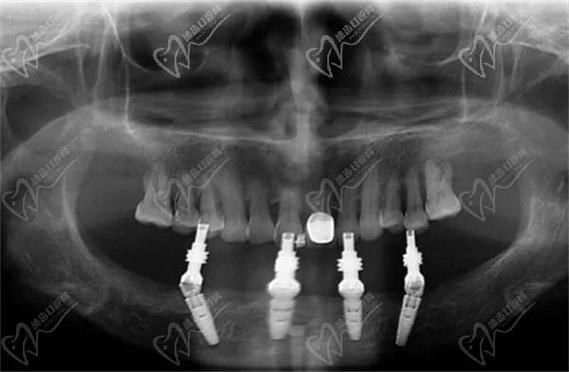

种植体植入:术中在牙槽骨上制备种植窝洞,按照植牙图设计的角度植入4颗种植体(常用直径4.0-5.0mm、长度10-13mm的钛种植体),前牙区垂直植入,后牙区倾斜植入,确保种植体尖端位于致密骨层以获得初期稳定性。

基台安装与临时桥修复:植入种植体后,安装愈合基台,取模制作临时固定桥,术中即刻佩戴,植牙图中会标注临时桥的咬合调整要点(如正中咬合无早接触、前牙引导无干扰)。

永久修复:骨结合完成后,更换愈合基台为永久基台,取模制作全瓷固定桥,试戴调整咬合后粘固,植牙图中会展示永久桥的边缘密合度、邻接关系及抛光效果。